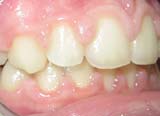

κλινική εικόνα ουλίτιδας περιοδοντίτιδα σε γυναίκα 22 ετών ακτινογραφική εικόνα περιοδοντίτιδας